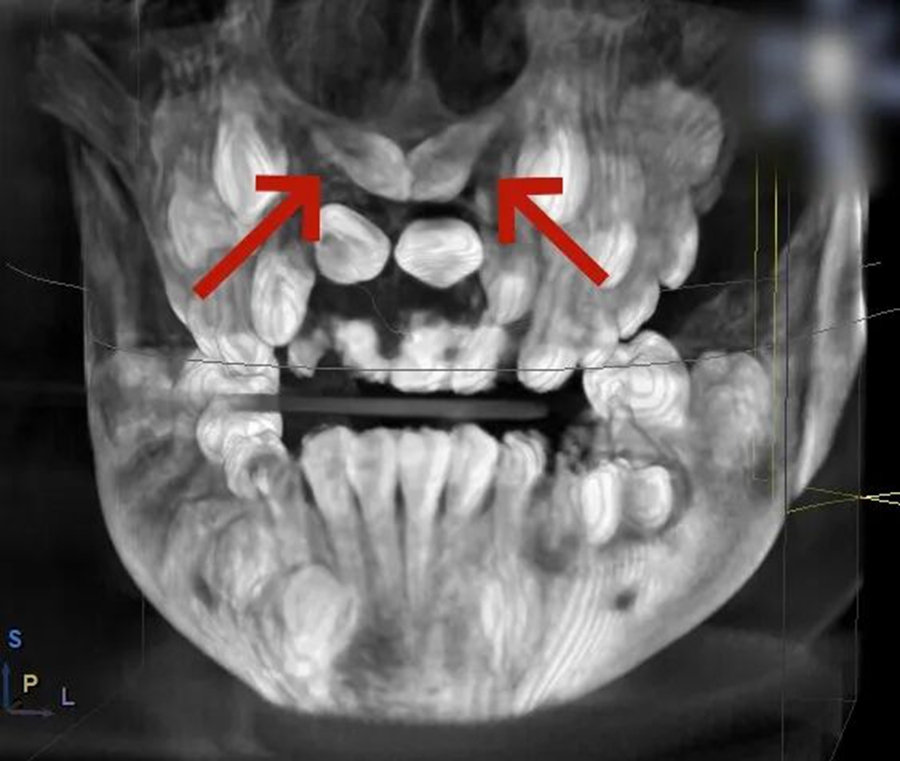

小胡已经9岁了,本该完成换牙的“新门牙”却迟迟没有萌出的迹象。家长带着他来到青岛市妇女儿童医院检查,拍摄 X 光片后发现,小胡的上颌骨内竟然埋伏着2颗多生牙,这两颗 "不速之客" 横着长在门牙牙根处,位置高至鼻底,还伴随唇向倾斜,阻碍了恒中切牙的正常萌出。

术前,医生通过 CBCT 扫描获取患者颌骨的精准立体影像,清晰定位埋伏牙的位置、形态以及与周围血管、神经的关系;随后在电脑上进行虚拟手术设计,规划出最佳的拔除路径,巧妙避开重要组织;最后通过 3D 打印技术,定制出完全贴合患者口腔结构的导板。这块小小的导板,就像是为手术钻头安装了 "GPS 导航",能在术中精准引导器械方向,让拔牙过程变得微创、安全、高效。

口腔团队经过全面评估和分析,最终为小胡确定了 3D 数字化导板引导的手术方案。